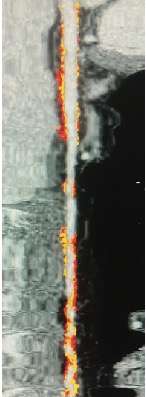

如下图一名 51 岁的男性因非典型胸痛而进行的带有斑块软件分析的定量 CT 扫描,

CT图显示了左前降支动脉斑块的自动化程度和亚型。

其中橙色表示非钙化斑块,红色表示定义为衰减小于 30 HU的低密度非钙化斑块。